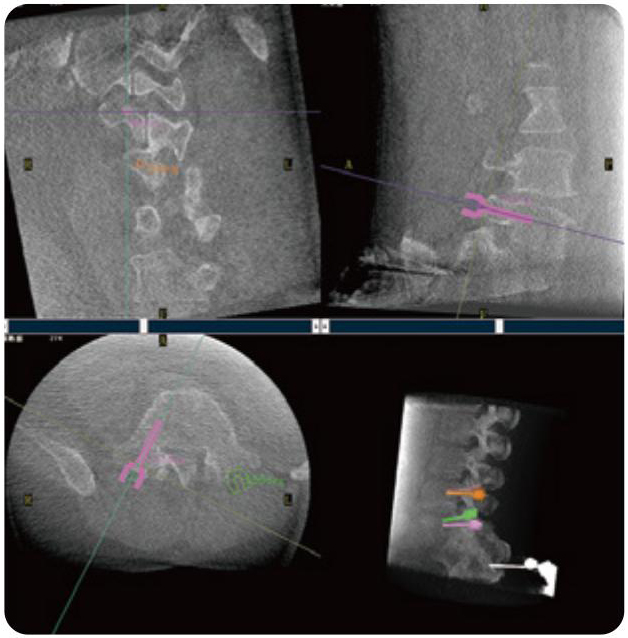

PL300B可應(yīng)用于多節(jié)段脊柱外科手術(shù),輔助醫(yī)生定位病灶部位,為脊柱外科手術(shù)(經(jīng)皮椎體成形術(shù)、椎弓根螺釘內(nèi)固定術(shù)等術(shù)式)提供術(shù)前手術(shù)流程規(guī)劃、入釘位置、角度可視化引導(dǎo),模擬仿真入釘輔助。

PL300B搭配普愛醫(yī)療自主研發(fā)生產(chǎn)的平板3D C形臂,借助一體化自適應(yīng)配準(zhǔn)( 軌跡配準(zhǔn))技術(shù),通過(guò)追蹤C(jī)形臂三維采集軌跡,自動(dòng)完成圖像坐標(biāo)建立和系統(tǒng)坐標(biāo)配準(zhǔn)。配準(zhǔn)精度更高,操作步驟少,系統(tǒng)運(yùn)作效率高。